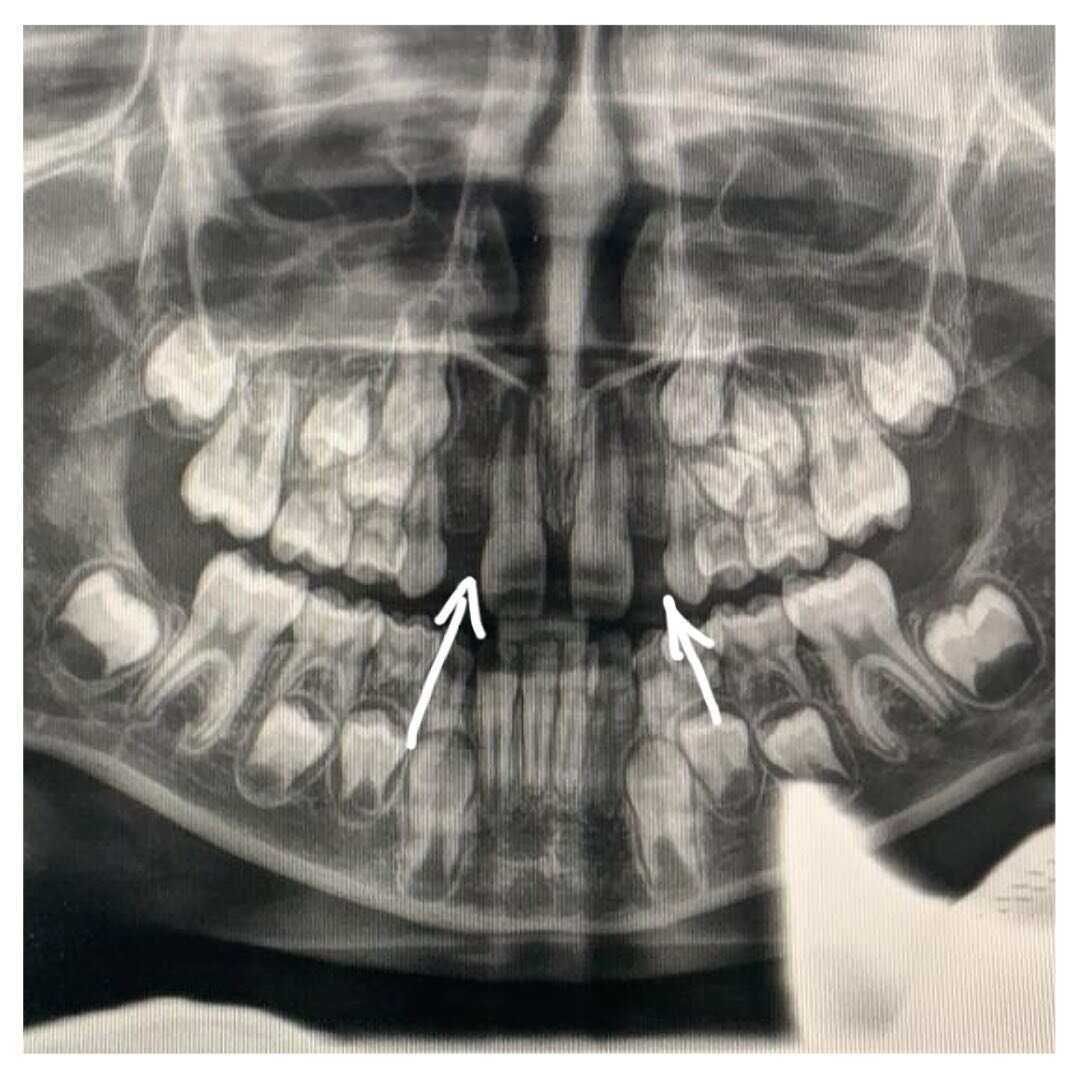

Молочные были, а постоянных нет. Как это случилось и что теперь делать? Об этом вам расскажет лечащий врач, ортодонт Оксана Журавская . Пациентке 7 лет. Ранее она лечилась в государственной клинике, теперь пришла в #ЦентрСелютиной. А произошло вот что: молочные боковые резцы на верхней челюсти выпали, а постоянные никак не растут. Долго ждать их не стали и пришли к нам. К слову, до этого девочке ни разу не делали общий панорамный снимок всех челюстей (ОПТГ). Поэтому и не знали, что зачатков постоянных резцов нет и ждать их появления бессмысленно. Почему это произошло, возможные причины: 1. Наследственный фактор; 2. Болезни матери в 1 или 3 триместрах беременности; 3. Прием антибиотиков во время беременности; 4. Болезни ребенка до 1 года. Какое лечение назначено? ✔Изготовлена пластинка-протез, которая будет замещать боковые резцы; ✔Так мы будем сохранять место в области отсутствующих зубов, чтобы соседние не сползли в образовавшуюся пустоту; ✔Расширяем верхнюю челюсть, т.к. есть суже

А произошло вот что: молочные боковые резцы на верхней челюсти выпали, а постоянные никак не растут.

К слову, до этого девочке ни разу не делали общий панорамный снимок всех челюстей (ОПТГ).

Поэтому и не знали, что зачатков постоянных резцов нет и ждать их появления бессмысленно.